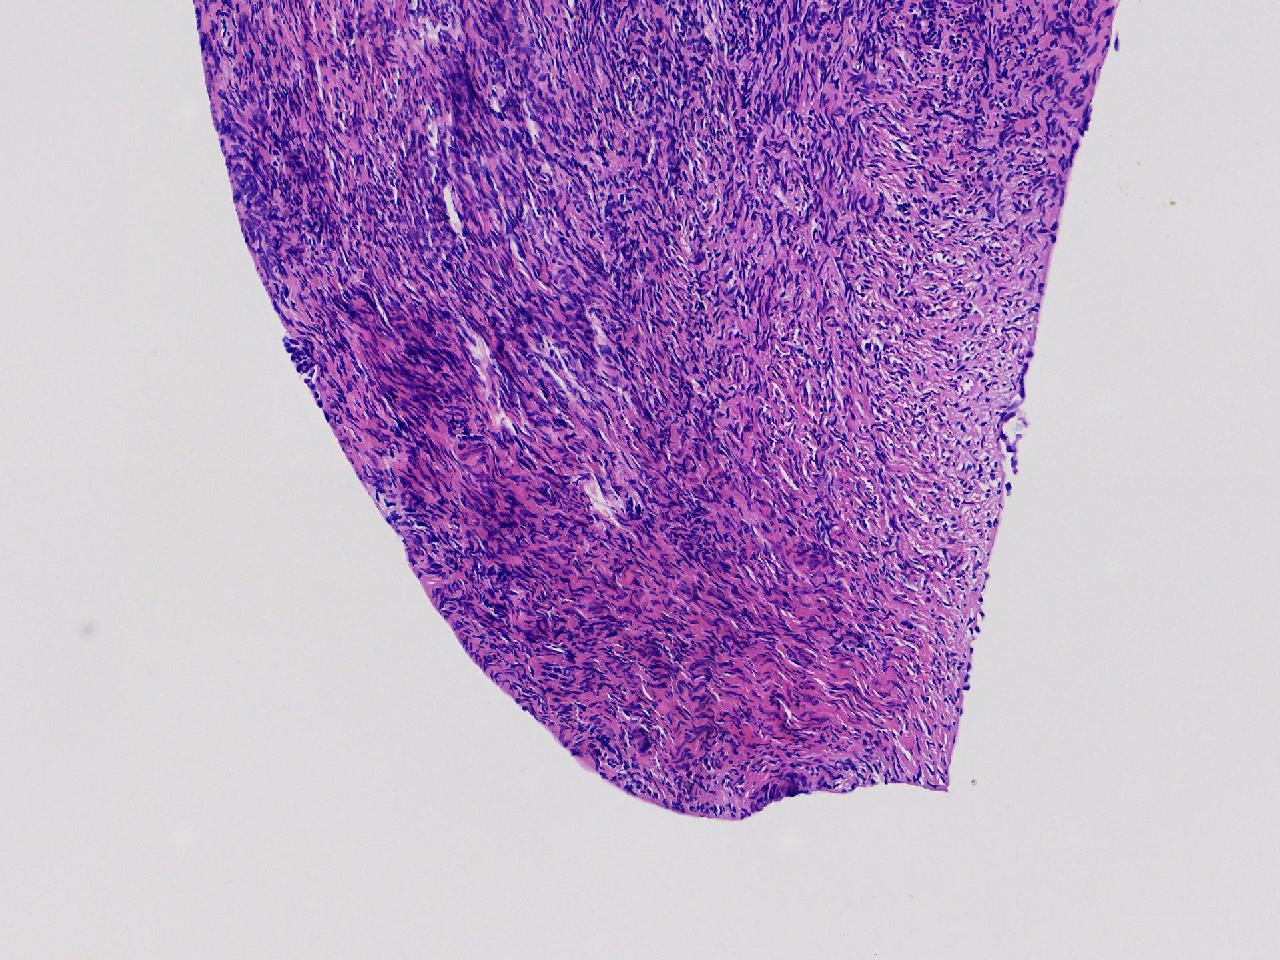

卵巢颗粒状突起活检。

女,34岁。右侧输卵管 异位妊娠,宫腔镜下见左侧卵巢颗粒状突起,取活检1块。

左侧卵巢颗粒状突起活检

灰白色不整形软组织1块,至今0.2厘米。

妊娠黄体瘤? 卵巢间质增生?

未见妊娠黄体瘤改变,见卵巢间质纤维增生。

卵巢间质纤维增生